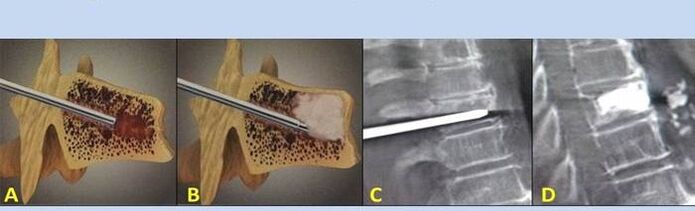

- Nucleoplasty– removal of the nucleus of the intervertebral disc.The operation relieves pressure on the nerve endings.

- Puncture vertebroplasty– method of stabilization of the vertebrae.During the procedure, the doctor fills the spinal cavities with bone cement.